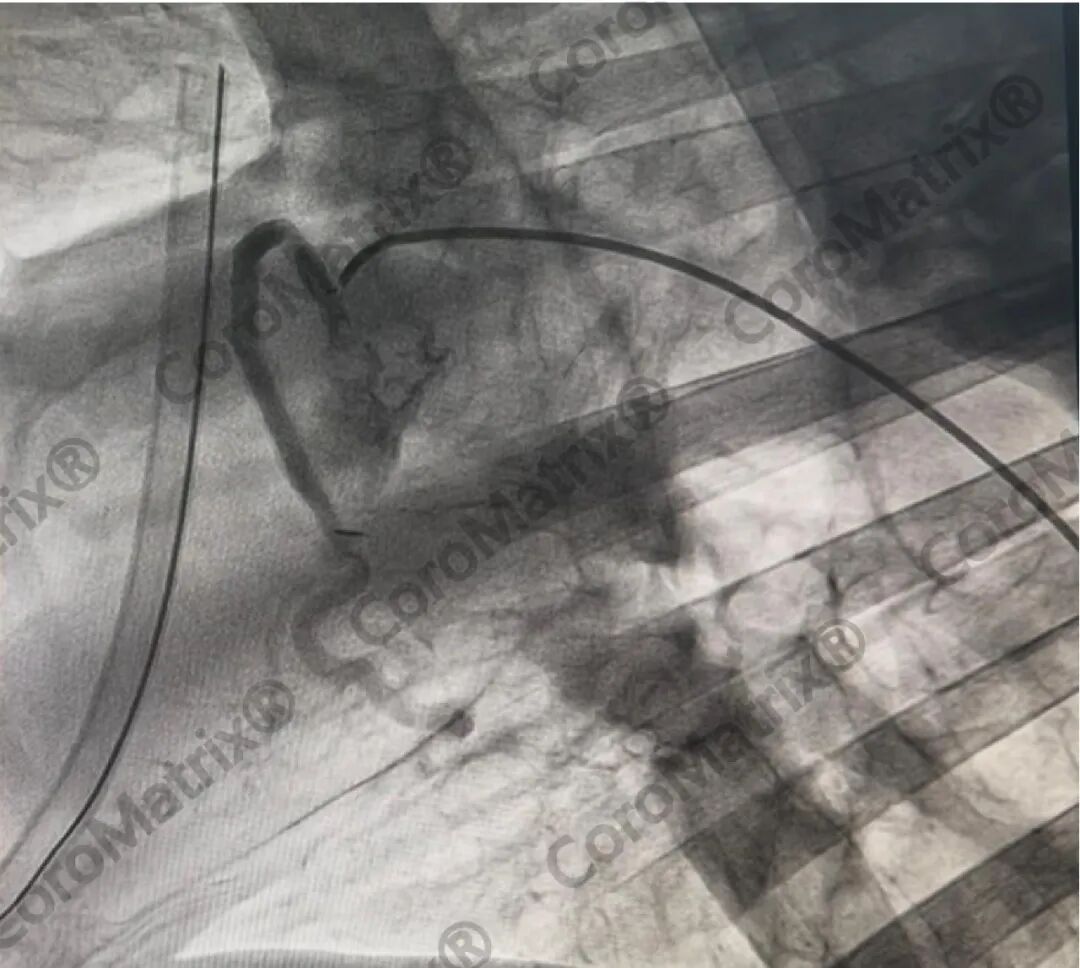

CoroMatrix蔻迈通人工血管用于羊冠脉搭桥术后DSA随访结果

最近Xeltis、Vascudyne分别公布了部分冠脉搭桥临床试验结果,Medical 21本月启动了欧洲临床试验,Humacyte计划2026年Q1-Q2启动临床试验。海迈医疗与国际同行同步,已经积累临床前大动物实验长期随访结果,预计2026—2027年启动3.5mm内径CoroMatrix蔻迈通生物型人工血管冠脉搭桥临床试验,而依据FDA指导原则,过去40年以来只要含高分子材料的传统人工血管严禁用于冠脉搭桥。